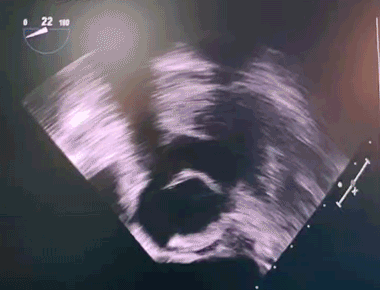

金晶主任凭借精湛的手术技术,联合麻醉科、手术室、体外循环科、超声科等多科室强大的协作实力,成功为患者置换了A23# 佰迈思®限位可扩张主动脉瓣,手术过程顺利。术中超声示人工主动脉瓣功能表现出色。患者切口仅约4cm,手术室即刻清醒,术后恢复良好。

超声示人工主动脉瓣功能表现出色